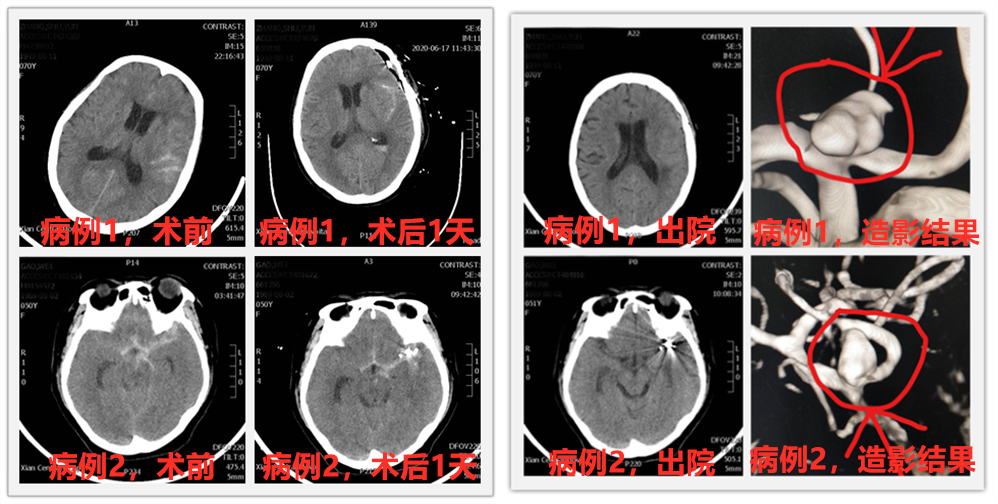

说完这么多理论,这不,西安市中心医院神经外科最近就有两位蛛网膜下腔急性出血患者,经过脑血管造影诊断,查出分别是颅内不同血管上的动脉瘤,根据病情需要及患者家属要求,科室施展十八般武艺对付这个“坏家伙”,分别为两位患者安排了开颅动脉瘤夹闭术及颅内动脉瘤介入栓塞术,经过积极治疗,患者都康复出院,回归正常生活,获得了患者及家属的一致好评。